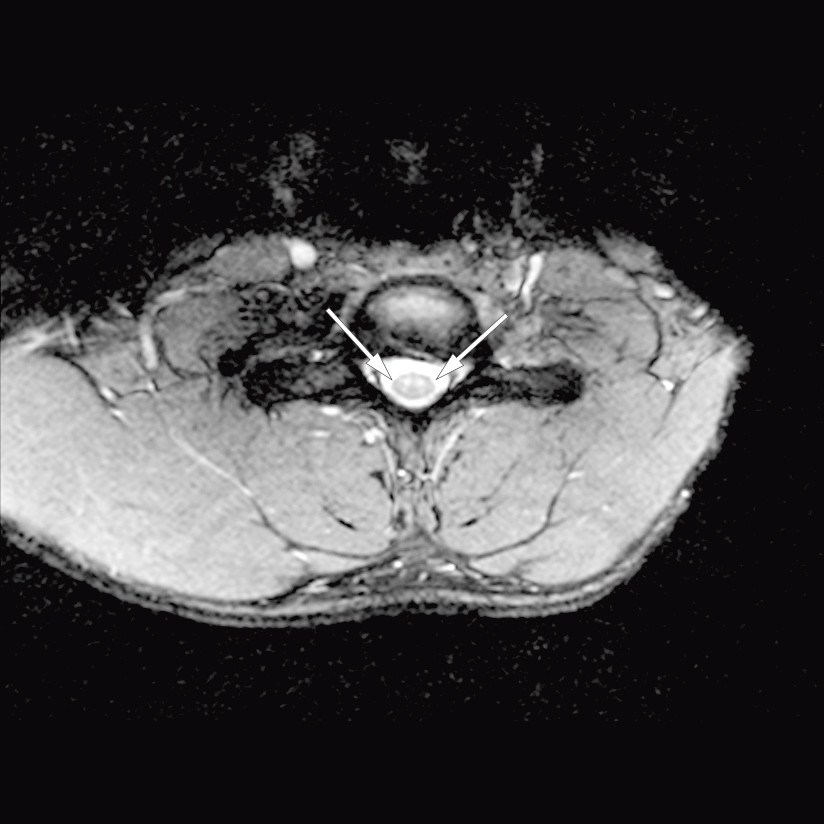

MR-undersøkelsen viste lav diffusjon ventralt i medulla fra nivå C5–Th1, utbredelse på nesten 7 cm (figur 1). Medulla var ikke svullen, og det ble ikke påvist kontrastopptak. På aksiale snitt (figur 2) var det i samme nivåer økt T2-signal i fremre horn bilateralt, såkalt slangeøyneutseende, forenlig med ett av de kjente mønstrene ved iskemi i forsyningsområdet til a. spinalis anterior. Funn med lav diffusjon med «vaskulær distribusjon» gav mistanke om cytotoksisk ødem på bakgrunn av fersk iskemisk skade. På dette tidspunktet var det ingen holdepunkter for infeksjon, da pasienten var afebril og hadde normale funn på blodprøver. Inflammasjon var fortsatt en mulig differensialdiagnose. Det var ingen signalavvik eller holdepunkter for infarkt eller annen patologi i cervikale virvelcorpora, men noe dehydrerte skiver. Senere samme dag ble det supplert med CT totalaorta, som ikke avdekket disseksjon, aneurismer eller annen embolikilde.